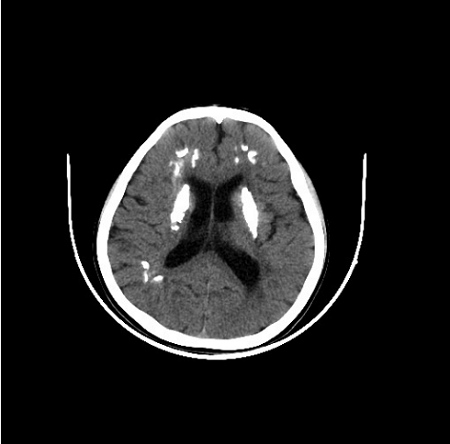

AGS临床表现非常的多样,个体间的差异也较大。多数患儿在3岁前就发病了,最常见的症状为颅内钙化、脑白质病变、脑萎缩,可伴有肌张力增高(就是肌肉紧张度增高)、运动发育落后、语言发育落后、小头畸形,伴或不伴智力发育落后等。其中颅内钙化在头颅CT上显示较清楚,多为双侧,主要分布于基底节区(图1)。脑白质病变在头颅MRI上显示较清楚,可累及脑室周围、皮质下白质、额叶和颞区等部位(图2)。脑萎缩主要显示为脑室周围区域和脑沟的扩大(图3)。也有患儿以反复发生冻疮样皮疹为突出表现,多发生在四肢末端、耳朵、面部和肘部等部位(图4),这些孩子的皮疹在冬天加重,气温变暖后可好转。如孩子出现上述症状,需及时到医院就诊。其他的临床表现还包括发热、癫痫、白细胞减少、贫血、血小板减低、转氨酶升高、肝脾肿大、肺部间质病变、甲状腺功能减退或者亚临床甲状腺功能减退、胃食管反流、关节肿胀或疼痛。轻度肺间质病变可以仅表现为肺部影像学的异常,严重者可以出现咳嗽、呼吸困难等症状。如果孩子出现了上述表现,家长切莫大意,要及时带孩子到正规医院就诊哦!

图2